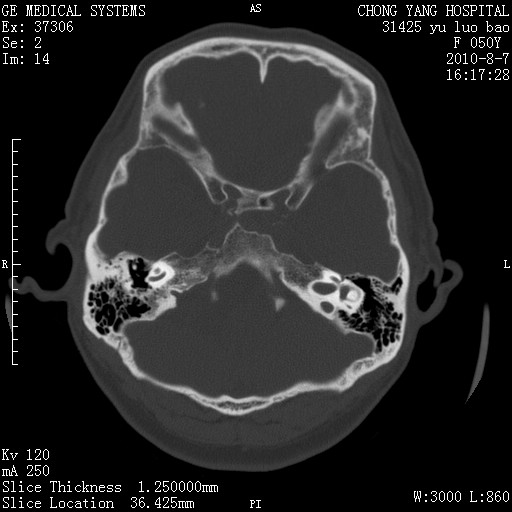

标题: CT28285:听力下降一年,头昏。

右侧桥小脑角去等密度占位,右侧内听道扩大、骨质吸收,考虑:右侧听神经瘤,建议增强检查。

右侧内听道扩大、骨质吸收,中脑受压左移,考虑:右侧听神经瘤,建议增强检查。支持!

骨窗示右侧内听道扩大,考虑右侧听神经瘤。

右侧桥小脑角区等密度占位,内耳道扩大,听神经瘤